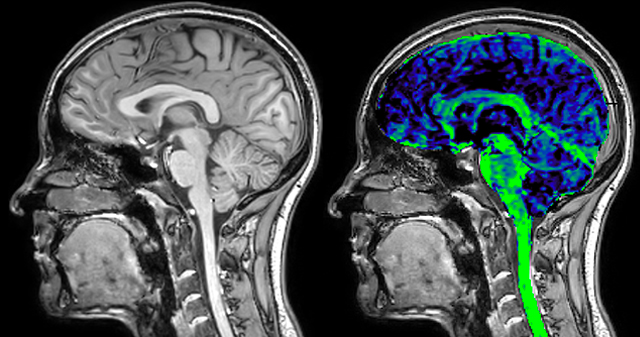

Dr. Rauscher says, “For MWI we perform 3D T2 with 32 or more echoes. This used to take a long time, but with Compressed SENSE we can decrease this to ten minutes for the whole head. Because of the large field of view (FOV) on the readout direction, we even get information from the brainstem, which we previously missed when we were using the GRASE approach. Having the whole head scan is nice because it has spatial resolution, orientation and FOV that are comparable to the standard 3D clinical MS scans, including the FLAIR and 3D T2, and a 3D T1 for brain volume.”

T1 - weighted

Myelin water imaging - T1 weighted

Myelin water imaging (echo 1)

Myelin water imaging with SENSE

Myelin water imaging with Compressed SENSE

With SENSE

With Compressed SENSE

Acquired resolution:

1 x 2 x 5 mm3

1.5 x 2 x 3 mm3

Number of echoes:

32 or 48

56

Echo spacing:

10 ms or 8 ms

7 ms

T1 - Weighted, Myelin Water Fraction Superimposed

MWI Spinal cord coverage

Spinal cord coverage

MWI Smaller, more isotropic voxels

Smaller, more isotropic voxels

MWI Excellent detail in quantitative maps

Excellent detail in quantitative maps

Images courtesy of Adam Dvorak, Department of Physics and Astronomy, University of British Columbia

20%

Myelin water fraction

0%